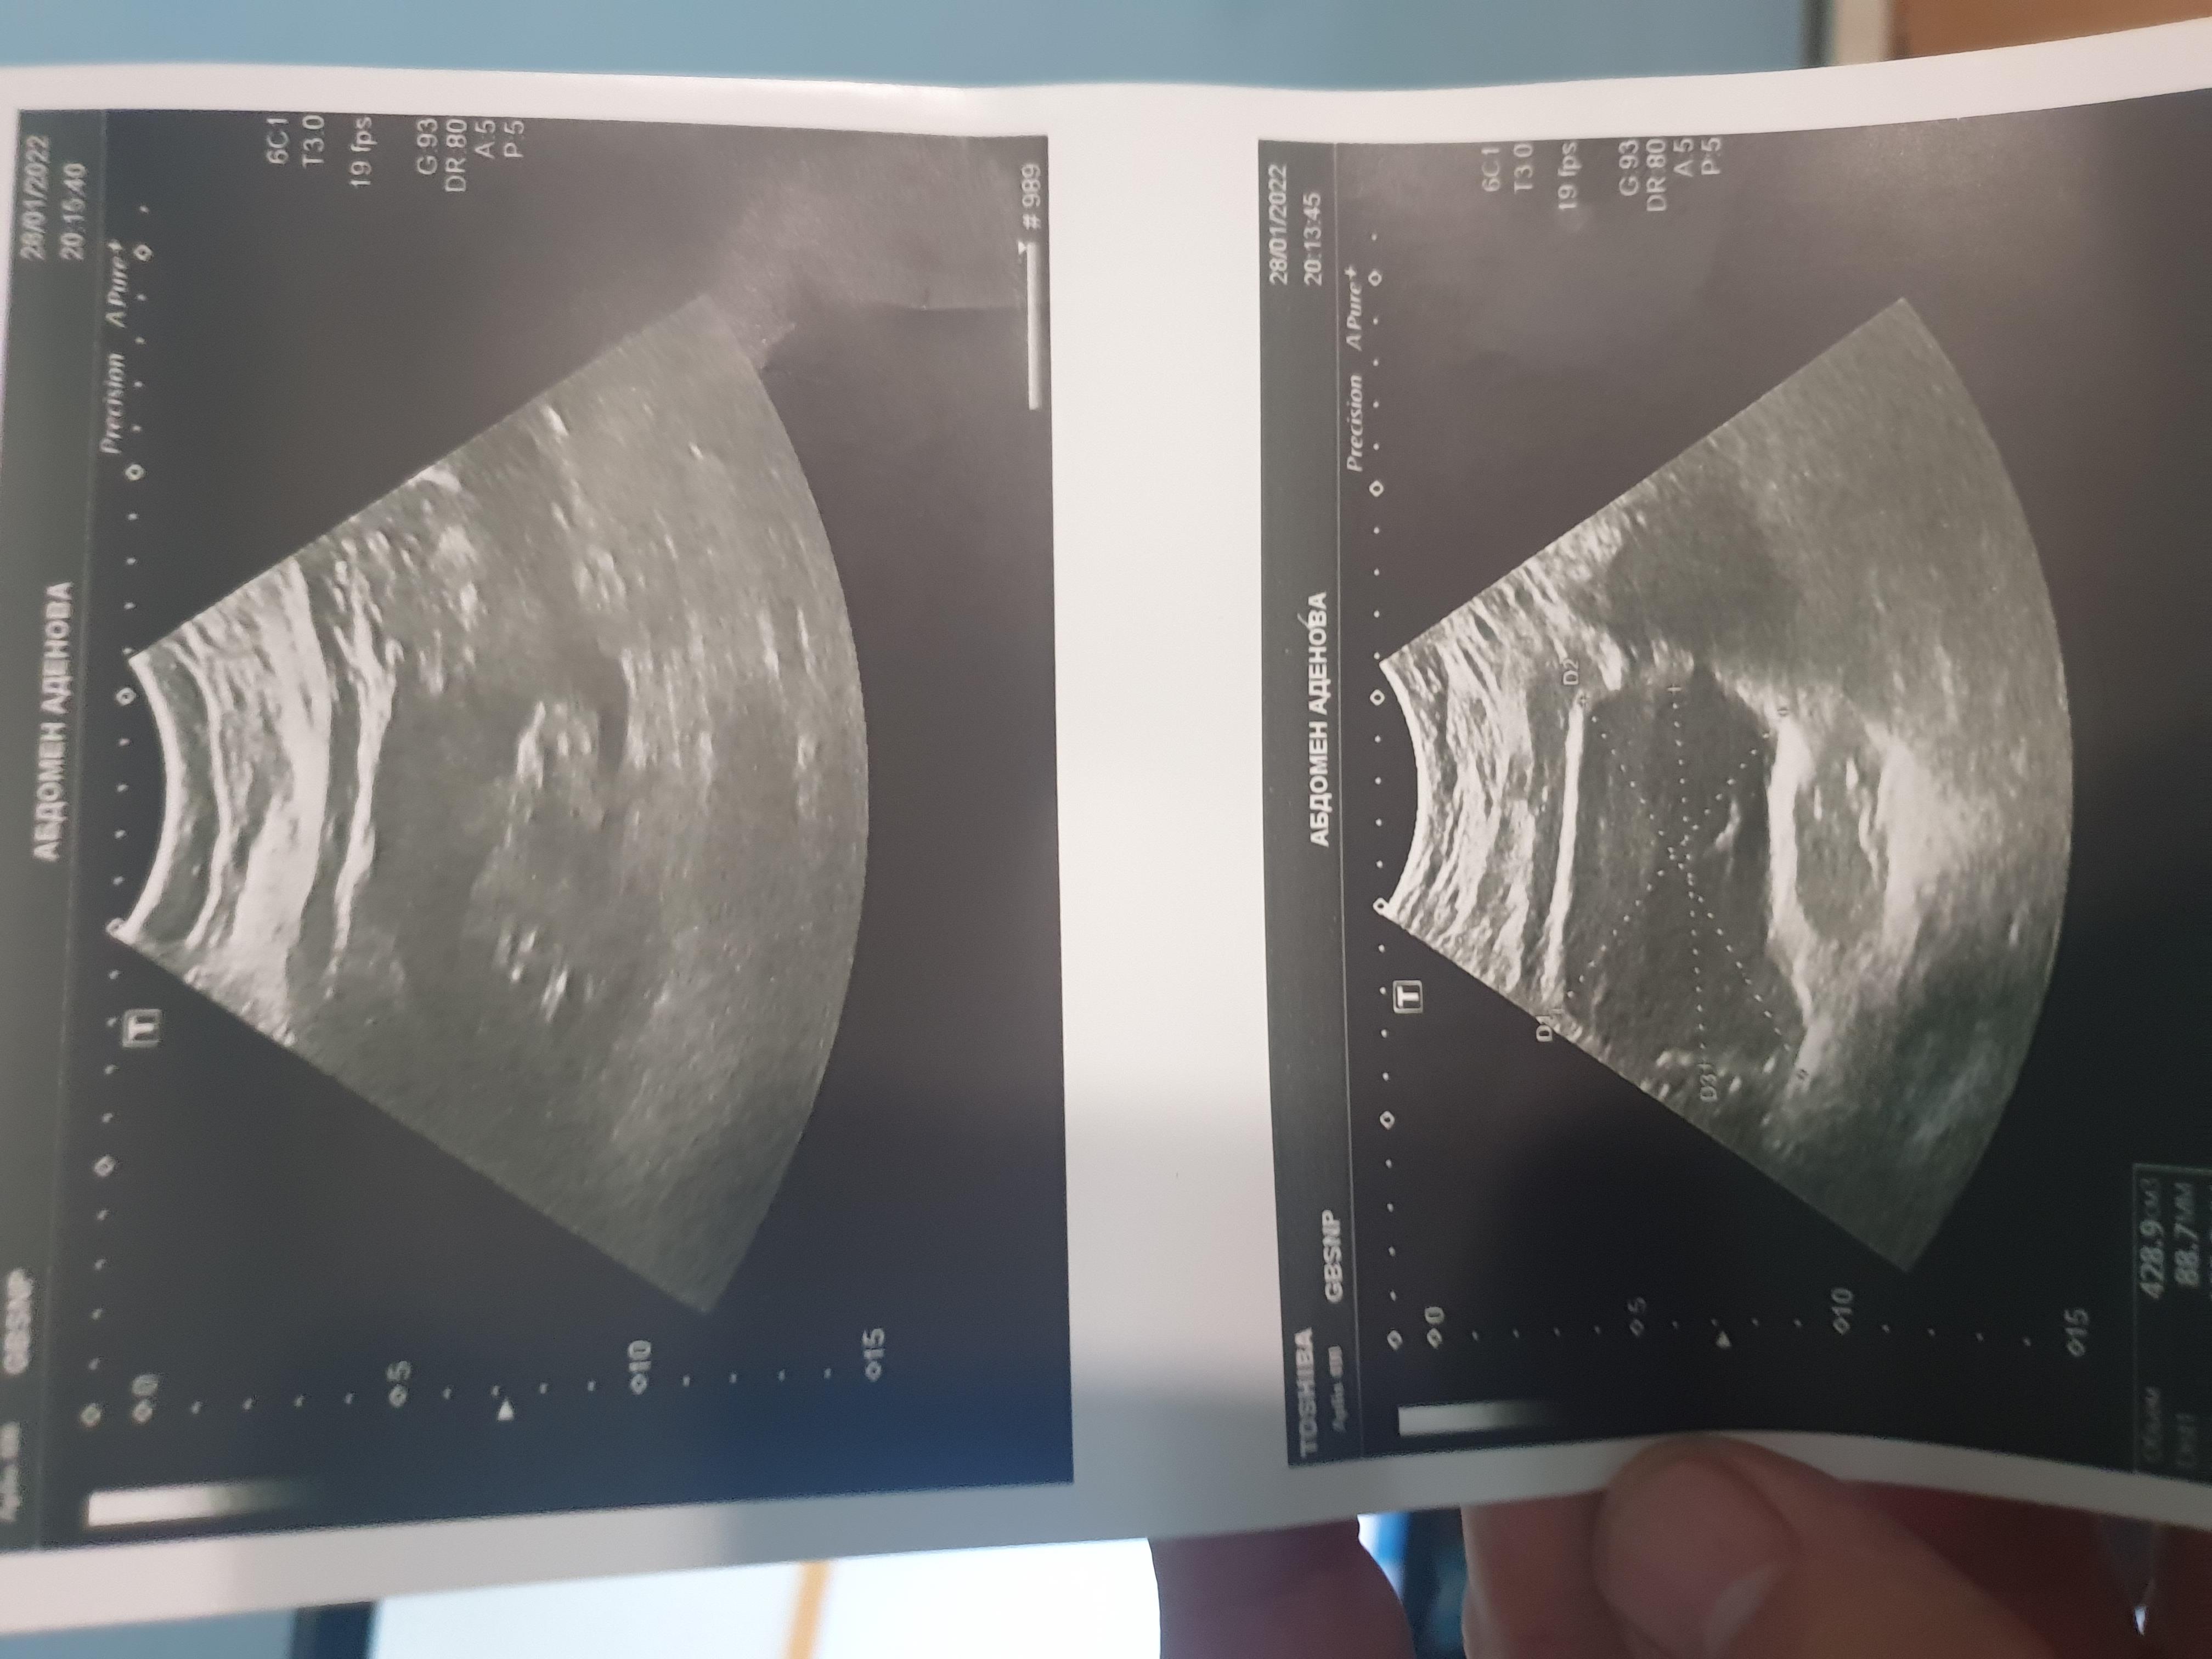

Добрый день.У жены было контактное дробление при помощи лазера, через уретру. Установили стент. Через 2 недели стент мигрировал в уретру, уже было видно трубочку, стент сняли. У жены сейчас сохраняются небольшие боли, мочеиспускание нормальное, температура максимум поднималась до 37, но сейчас имеется тошнота и иногда рвота, но это сетуем на пищевое отравление и несварение, пару дней назад. Моча нормального цвета. К сожалению к урологу попасть не можем. Как определить нет ли инфекции? Потому что стент просто вытянули из уретры, может повредили, стенки мочеточника? Прописали Фурамаг и цицибон. Может нужны антимикробные? Температура держится 37

Здравствуйте! Основной вопрос - это проходимость мочеточника. На представленном узи почки - имеется расширение лоханки почки. Надо повторить УЗИ почки. При сохраняющейся пиелоэктазии - свяжитесь с оперирующим хирургом. Удачи!